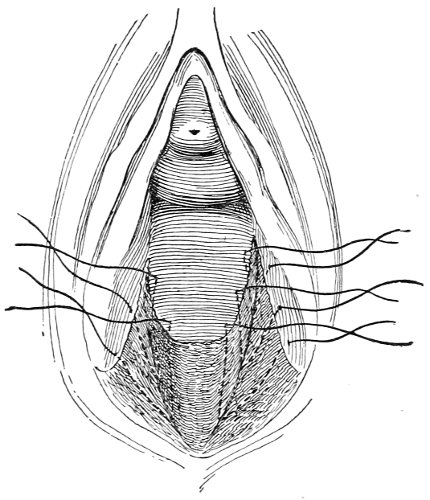

An accurate knowledge of the anatomy and mechanism of the female perineum is essential to an understanding of the nature and treatment of injuries to this structure. The anatomical structures lying between the anus behind and the symphysis pubis in front are those that most directly interest the gynecologist. Proceeding from 57 below upward, we find the following structures lying in superimposed planes: the skin, the superficial fascia, the deep layer of the superficial fascia, the transversus perinæi and the sphincter vaginæ muscles, the anterior layer of the triangular ligament, the posterior layer of the triangular ligament, the levator ani muscle (Fig. 19).

Fig. 18, A.—Superficial structures of the female perineum (Weisse).

Fig. 19.—Dissection of female perineum: on the left side the perineal muscles are exposed by the reflection of the perineal fascia; on the right side the muscles and the superficial layer of the triangular ligament have been removed, thereby exposing the deep layer of the ligament. S. V., Sphincter vaginæ muscle.

The vagina passes through these structures. They surround and support the ostium vaginæ as the fascia and muscles surround and support the opening of the rectum or the anus. The muscles and fasciæ are attached in the median line between the anus and the vagina, and therefore this part of the body, which is called the perineum, is supported or maintained in its 58 proper position by these various structures. The transversus perinæi arises from the ramus of the ischium and is inserted in the perineum. The bulbo-cavernosus, or sphincter vaginæ, arises in the perineum and is inserted in and about the clitoris. The inner fibers of the levator ani arise from the symphysis pubis and are inserted in the perineum and the lower part of the vagina (Fig. 20). When these muscles contract, their action, therefore, is to draw the perineum upward and forward. At the same time the anus is drawn upward and forward, and so also is the posterior margin of the ostium vaginæ and the lower portion of the posterior vaginal wall.

Fig. 20.—Dissection of female perineum, showing the deeper structures after removal of the levator and sphincter ani muscles.

The vagina has no circular sphincter like the anus, but 59 the vaginal month is kept closed by the action of the transversus perinæi, sphincter vaginæ, and levator ani muscles, which draw the perineum forward, and thus keep the posterior vaginal wall in apposition with the anterior wall.

Fig. 21.—Muscular floor of the pelvis seen from above.

This sling of muscles and fascia, which surrounds and supports the opening of the vagina, may readily be felt in the nulliparous woman by introducing the finger in the vagina and pressing backward and outward toward the ischio-rectal fossa. We then feel plainly, immediately within the ostium vaginæ, a firm resisting band of tissue, apparently about half an inch broad, embracing the posterior portion of the lower vagina. This band is formed by the inner edges of the various muscles and planes of fascia that have been described.

Fig. 22.—Sagittal section showing relations of the several layers of fascia within the pelvic floor (Dickinson).